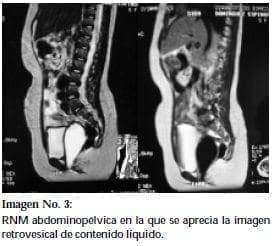

RNM abdominopélvicaPaciente de 8 años de edad. Hallazgo incidental de agenesia renal derecha en ecografía realizada por cuadro de dolor abdominal secundario a intoxicación exógena. Su vía urinaria fue estudiada demostrándose adicionalmente la presencia de reflujo vésico renal izquierdo grado II/V con DMSA normal. Ecografía pélvica demostró masa retrovesical de 86 x 49 x 50 mm compatible con hidrocolpos y/o mucocolpos. Se realizó inicialmente tomografía axial computarizada y luego RNM abdominal y pélvica en la que se evidencia imagen retrovesical piriforme de 140 x 40 x 45 mm de paredes delgadas y contenido líquido que se extiende hacia la vagina (Imagen No 2 y No 3). Al examen físico no se evidencia el introito vaginal y no hay abombamiento evidente compatible con himen imperforado. Se considera el caso compatible con la presencia de una tabique vaginal transverso por lo cual se programará para examen bajo anestesia y vaginoplastia.